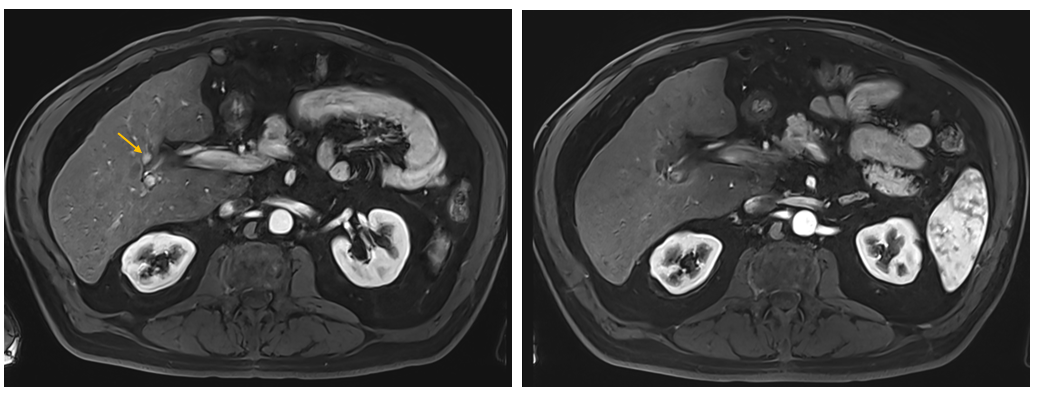

AblaSure showing a complete treatment of the tumor and margins (100% lesion, 98% margin)

MRI Follow-up at 8 weeks showing complete treatment

- AblaSure® analysis demonstrated what appeared to be complete coverage of the lesion and 98% coverage of the margin.

- Follow-up imaging confirmed full coverage of the treated lesion, with the appearance of a new LI-RADS 3 lesion currently under surveillance.